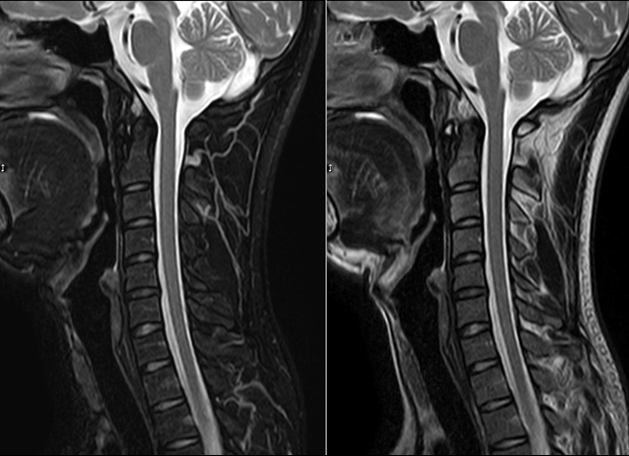

颈椎磁共振(mri)解剖——矢状面

mri 下脊椎基本解剖集锦:颈椎

颈椎mri解剖与常用数据ppt

颈椎mri:颈5-6椎间盘突出,椎管狭窄,脊髓信号缺血改变.